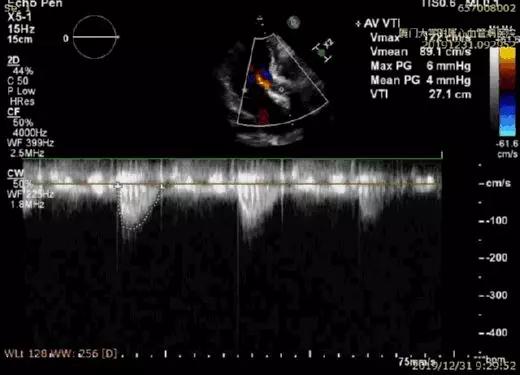

术后超声显示压差明显降低

不到2小时的手术时间,王焱院长带领的心脏团队成功完成了TAVI手术。陈奶奶主动脉瓣重度狭窄的情况得以解除,主动脉根部-左心室压差由术前的74mmHg降到了4mmHg,患者左心功能恢复正常,术后即撤除了IABP。